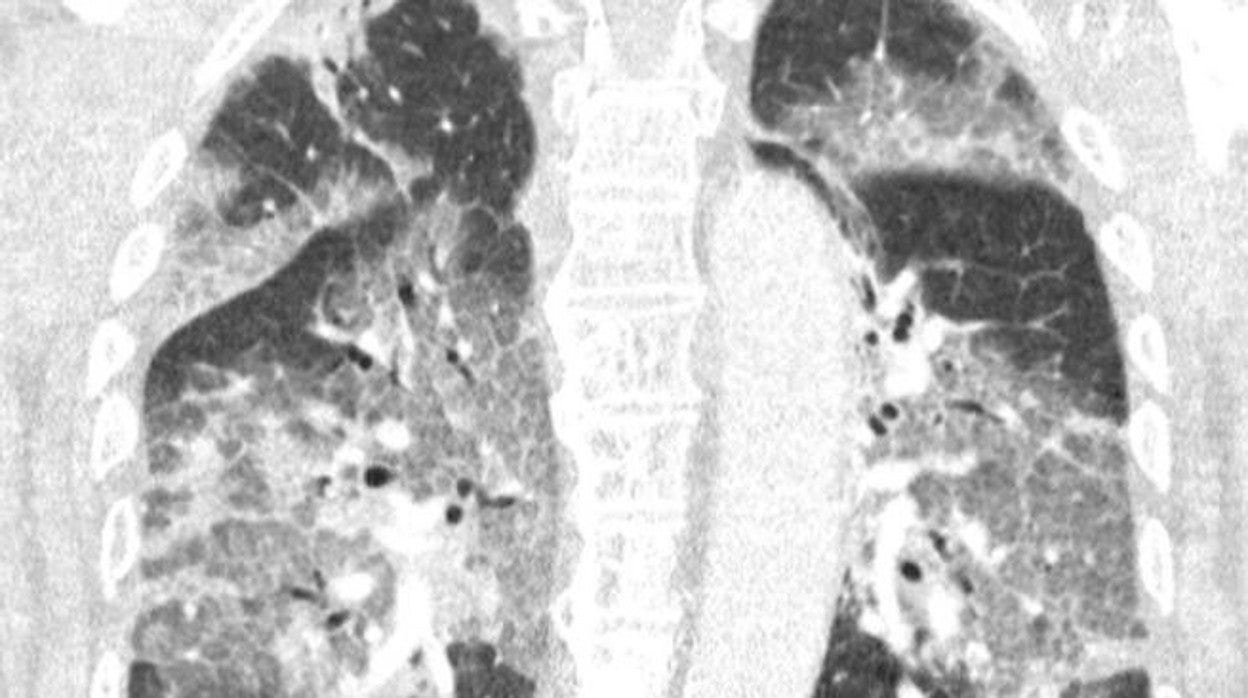

Radiografía de los pulmones del paciente que terminó en la UCI con neumonía Vídeo: Morir por COVID es 2.300 veces más probable que hacerlo por la vacuna - Atlas

En la carta relatan el ingreso en la UCI de un paciente que se ha negado a recibir la vacuna de AstraZeneca . Comentan con detalle cómo lucha por su vida, conectado a la respiración asistida: «Oímos el tremendo pesar en su voz y la desesperación en sus ojos. El virus lo ha atacado y podría haberse evitado. Con su permiso, compartimos su escáner de pulmón. No es necesario ser un especialista en pulmones para reconocer la devastación, ni epidemiólogo para explicar los riesgos de no estar vacunado».